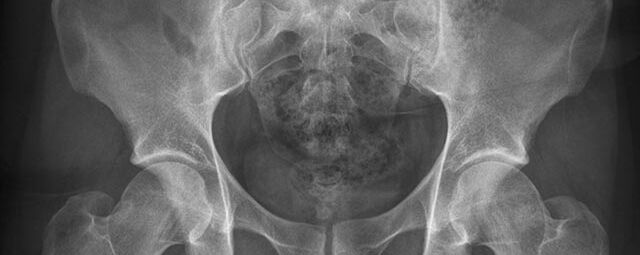

Röntgen Bauchorgane

• Ileus

• Verdacht auf Perforation von Teilen des Magen-Darm-Trakts

• Nierensteindiagnostik